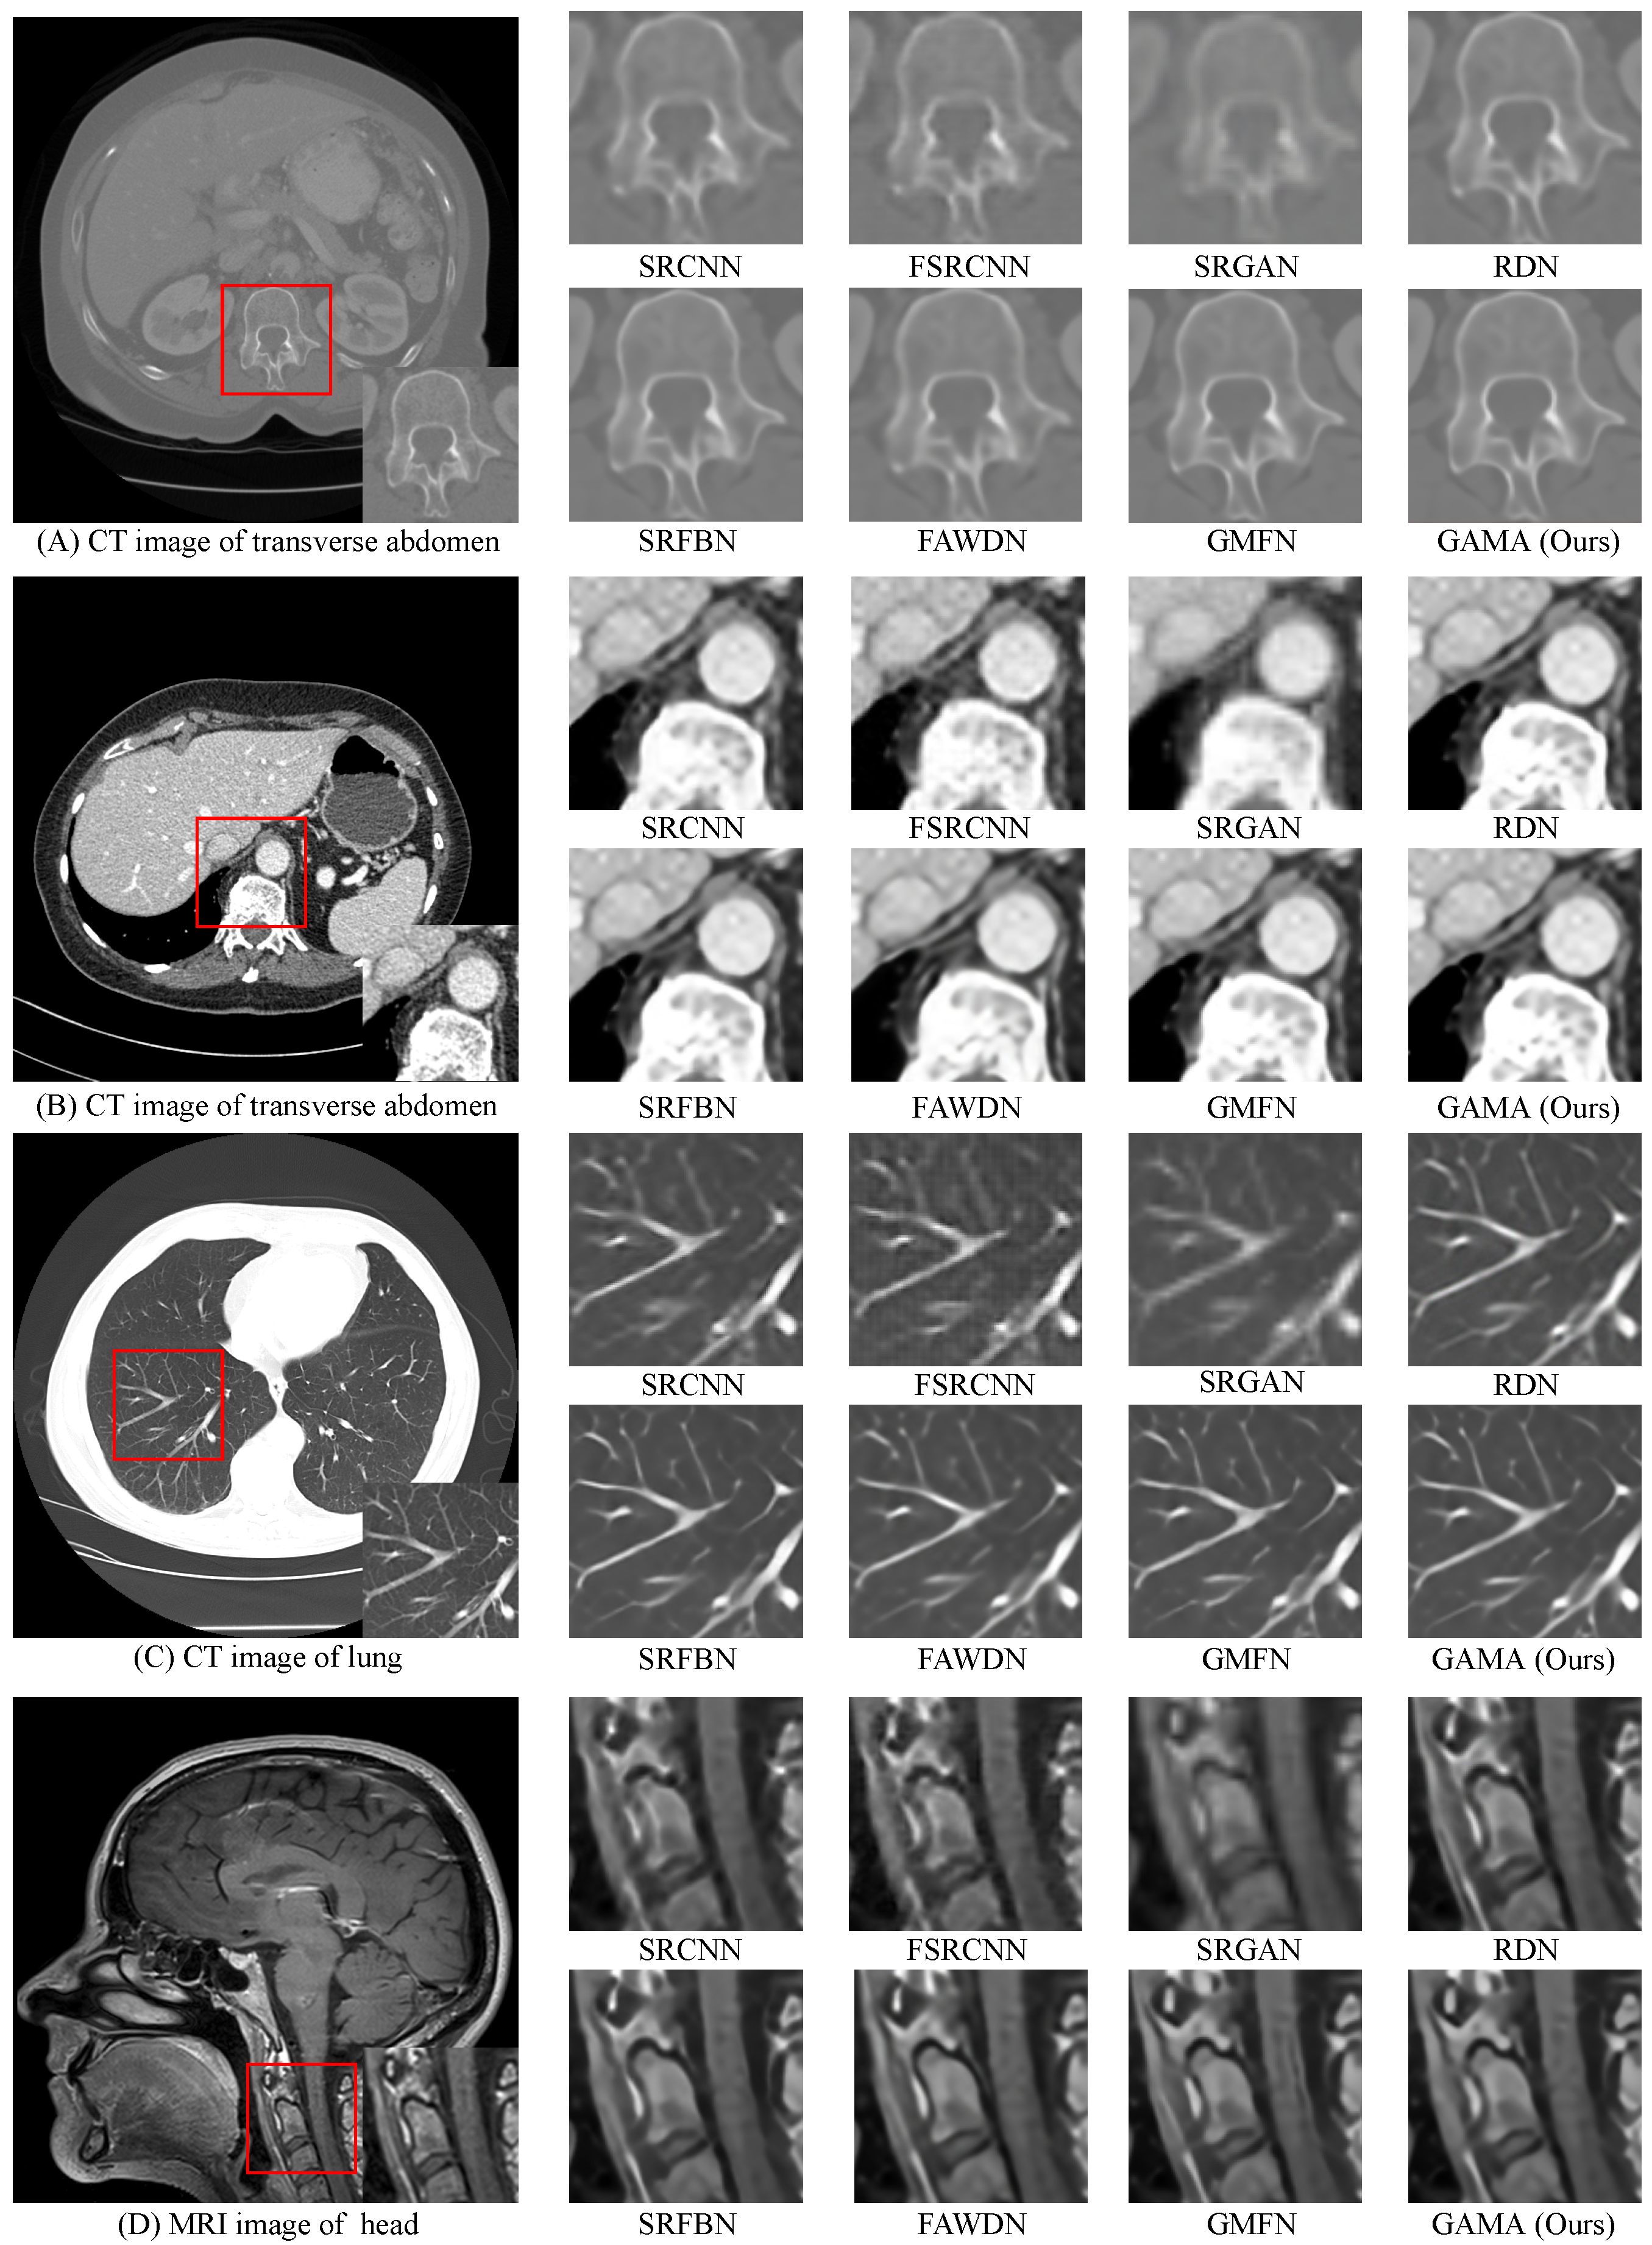

4.4. Comparative Analysis